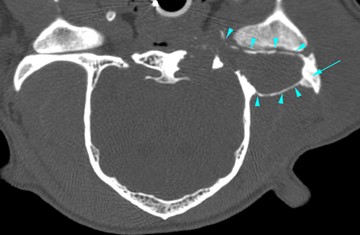

The expansion of the dorsal wall of the tympanic bulla, had a mass effect on the brain. A severe expansile process was also seen at the level of the left zygomatic process (cyan arrowheads), causing a reduction of the left temporomandibular joint intra-articular space.